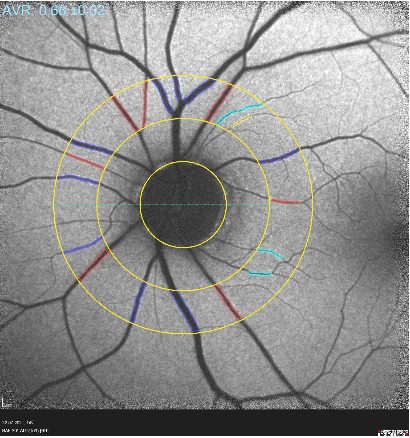

Durchblutungsmessung